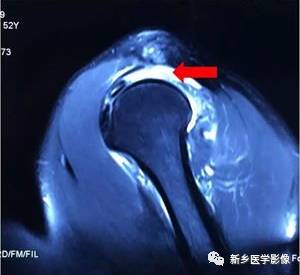

病例一:

红色箭头:冈上肌腱滑囊层撕裂